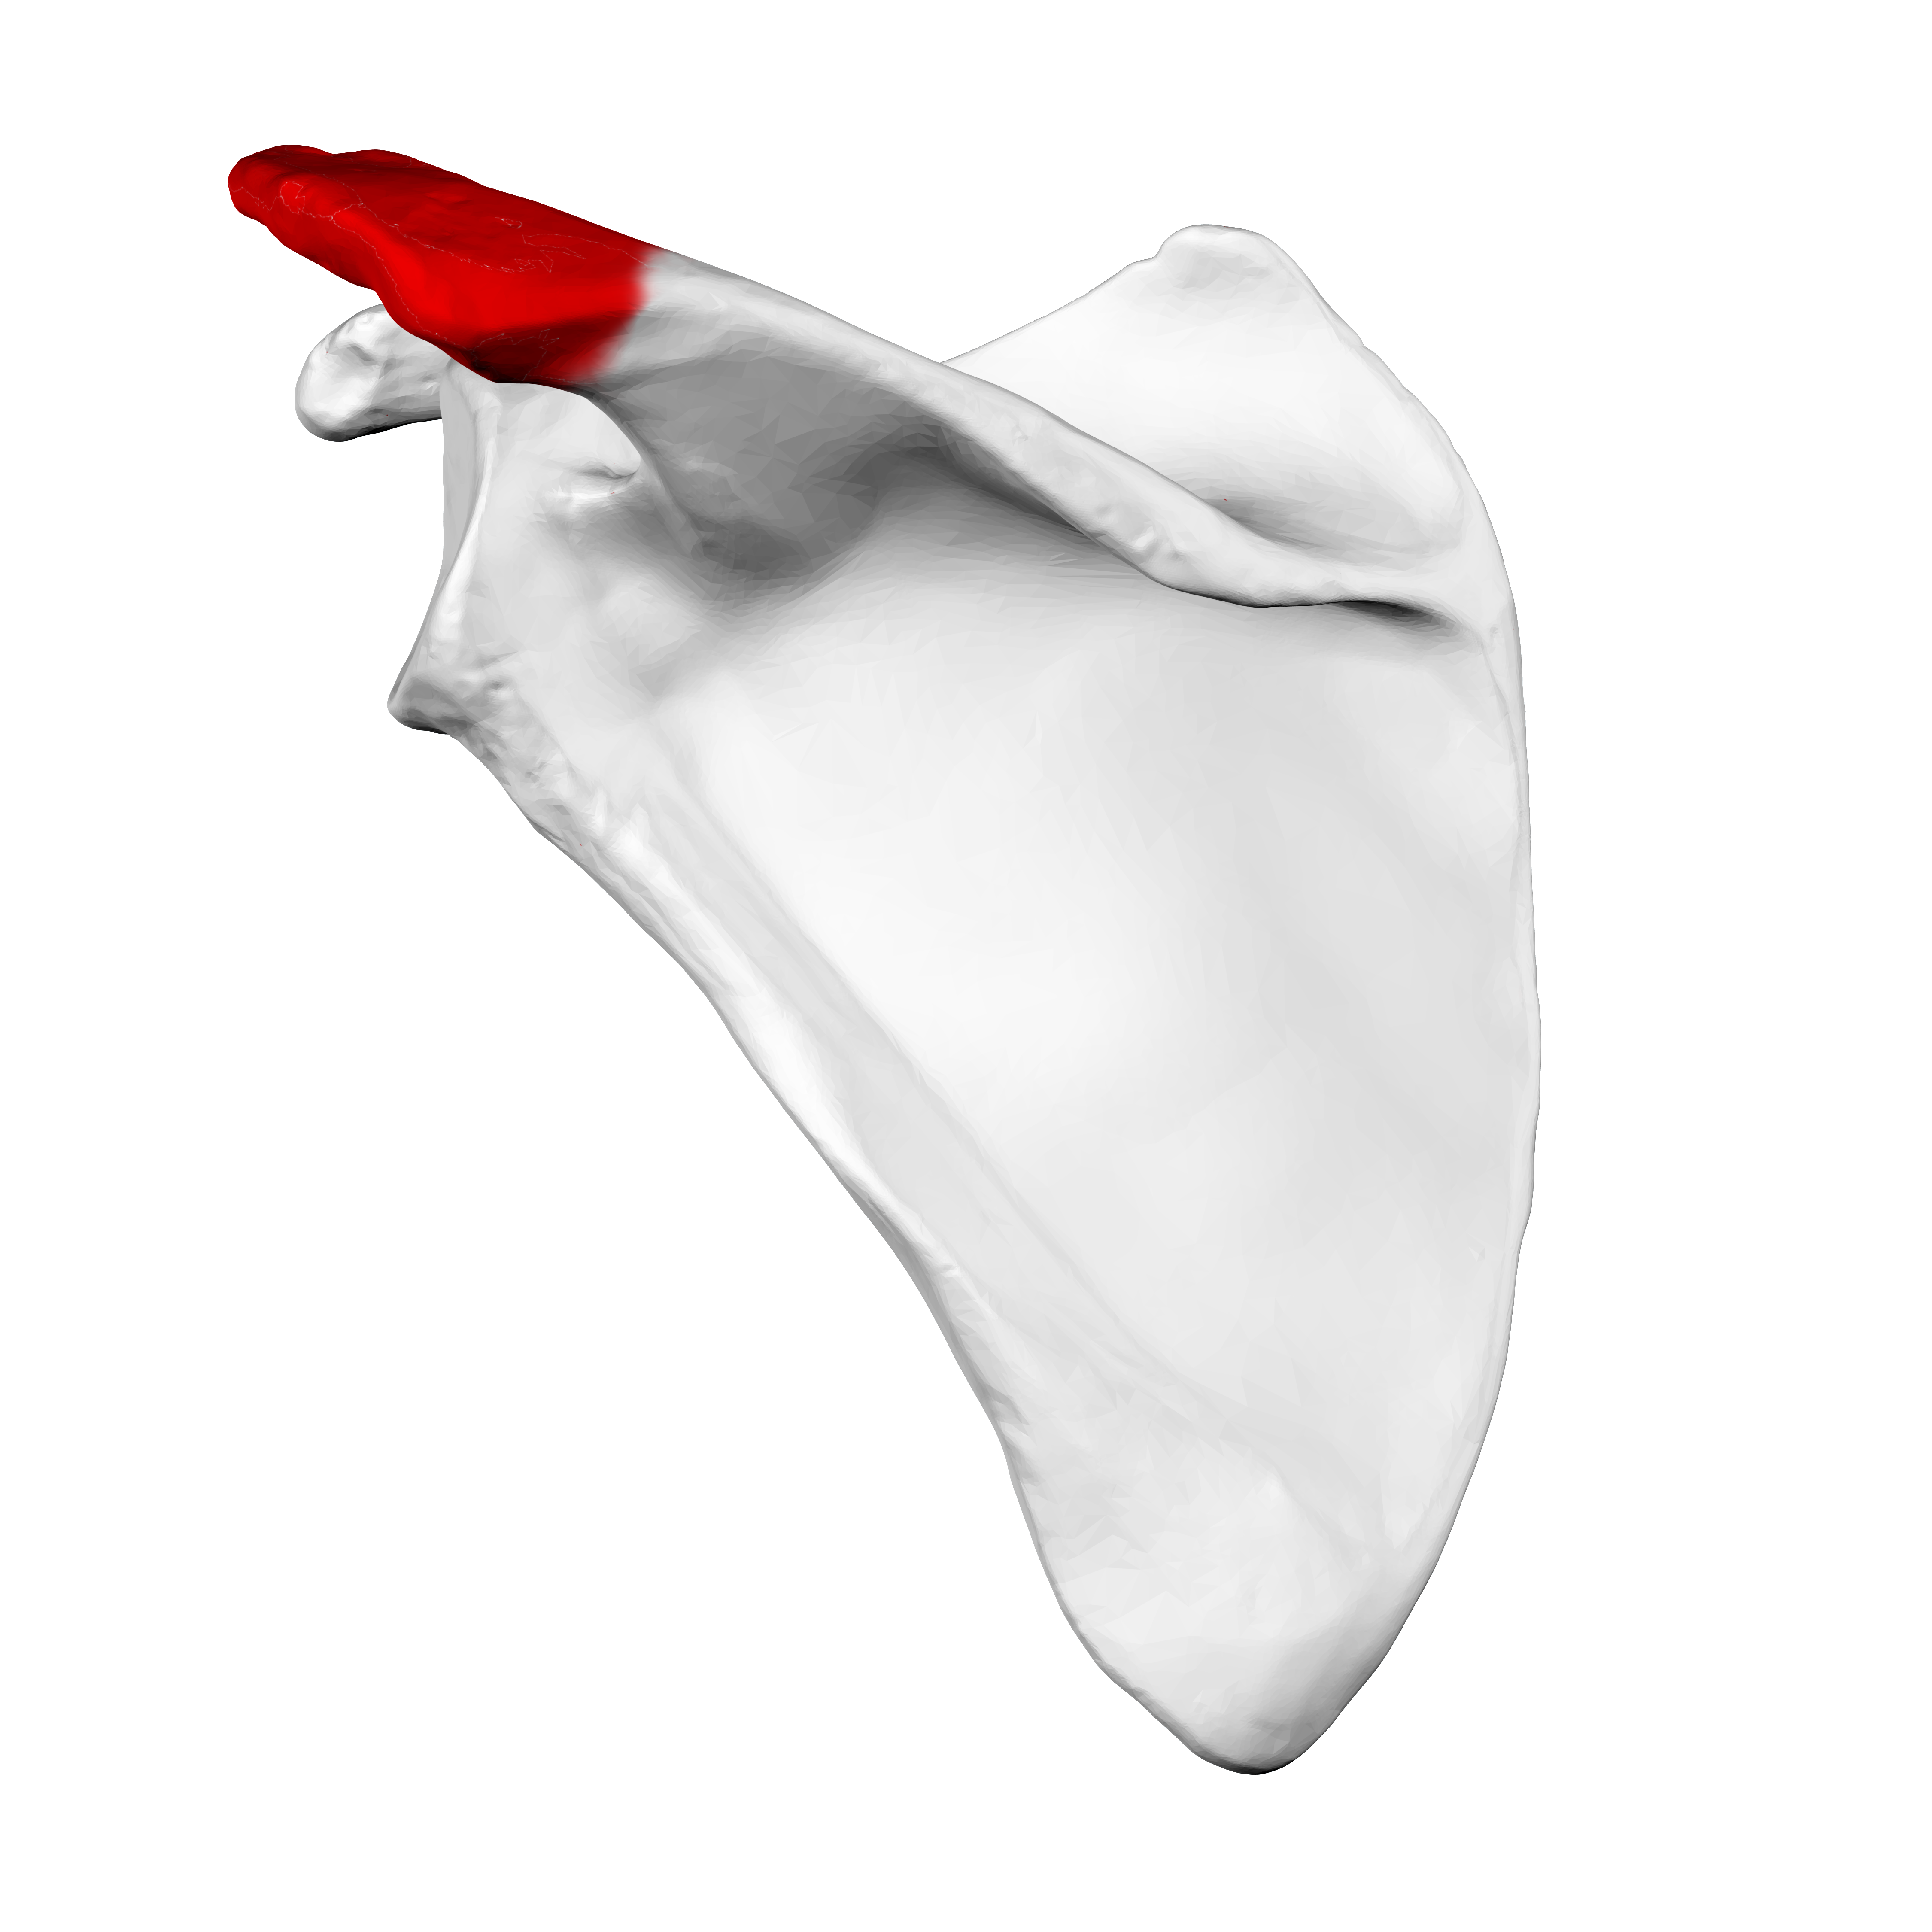

scapula

acromion

bones of human shoulder